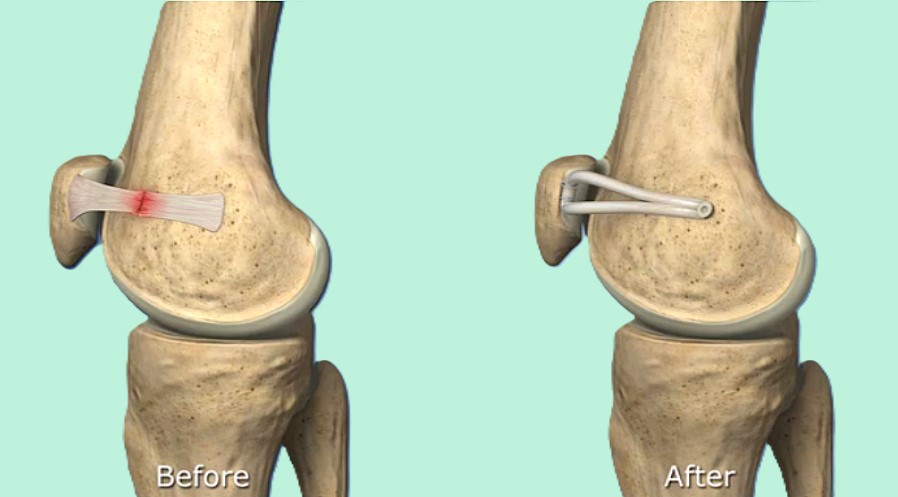

内側膝蓋大腿靱帯(MPFL)再建術

横浜整形外科野村院長は世界で最も早く膝蓋骨脱臼に対するMPFL再建術を開発し現在まで500例以上の手術を行ってきました。この数は世界トップクラスです。

再建材料として1997年まで人工靭帯法、1998年に自家腱法を開発しました。手術結果は世界的雑誌 The Knee、Arthroscopy、AJSMに4つ論文が掲載されました。採取する腱の半腱様筋腱や薄筋腱は採取しても運動機能に影響はありません。人工靱帯法でも組織学的に良好な靱帯が再生されることが判明しています。世界的雑誌AJSMのレビュー(Bucken 2010,AJSM)ではMPFL再建術の2009年以前の世界の論文から信頼できる論文は12個のみであり、その内野村医師は2000年に世界で最初に信頼できる論文を発表したと記載されています。12個の内3個の野村医師の論文が選ばれています。

2022年最新手術法開発

術後スケジュールは手術2~4日目に杖なしで退院・術後リハビリ通院不要・ランニング2ヶ月~、スポーツ3ヶ月~。世界で最も早いリハビリを達成。